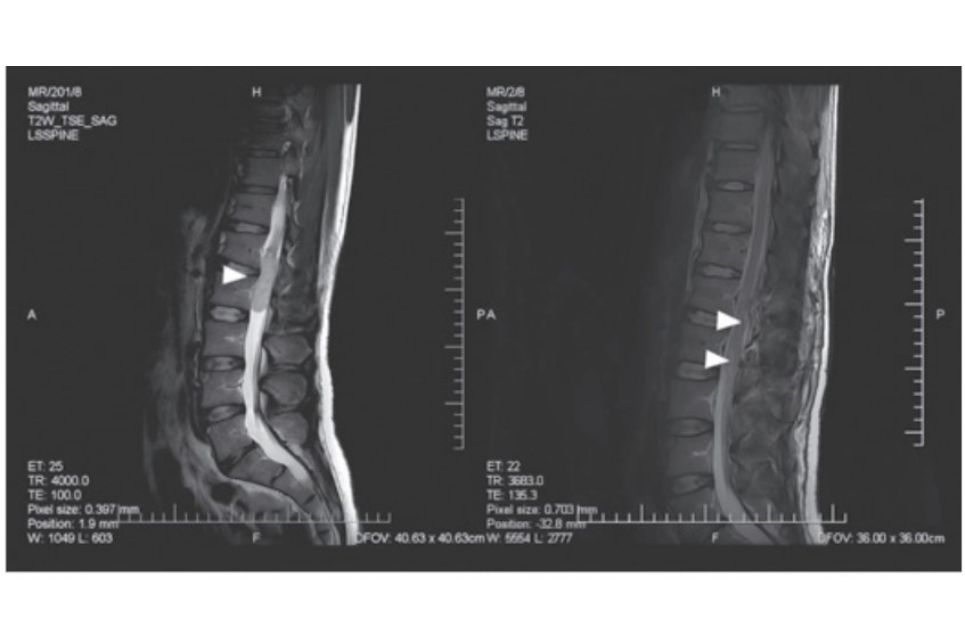

Femoropelvilumbální komplex má zásadní význam pro držení trupu a postavení dolních končetin. Orientace pánve v sagitální rovině určuje jak různé rentgenologické typy zakřivení páteře, tak i různé typy držení těla, které hodnotíme vizuálně a palpačně při fyzikálním vyšetření. Více...